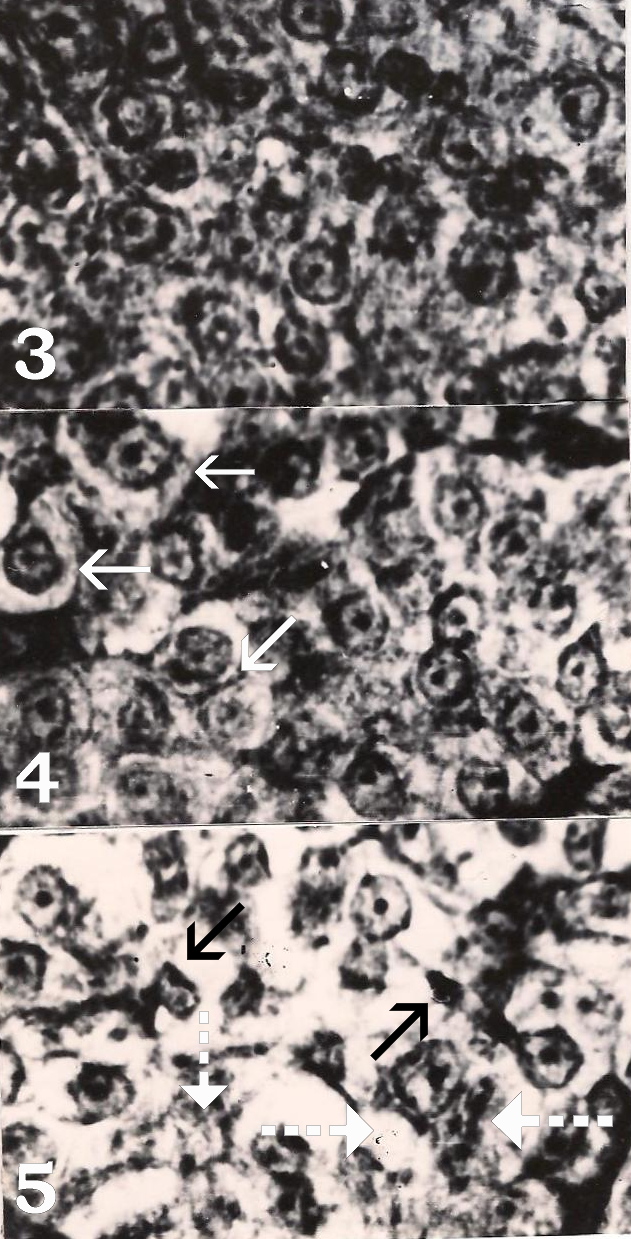

- Figure 3. Prolactin cells of control Heteropneustes fossilis. Mark indistinct cell boundaries. Herlant tetrachrome X 800. Figure 4. Prolactin cells of 21 days chlorpyrifos treated fish showing slight degranulation (arrows). Herlant tetrachrome X 800.